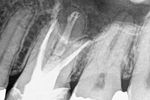

Revisionsbehandlung eines Unterkiefermolaren (37) vor geplanter Überkronung (Dr. Maik Göbbels) Download